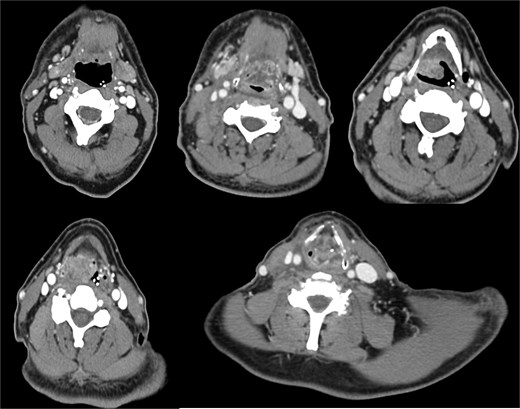

A 64-year-old male, a former alcohol user and non-smoker, presented with a two-month history of painful dysphagia and mild dyspnea. Fiberoptic laryngoscopy revealed an exophytic mass arising from the right aryepiglottic fold within the supraglottic region. The true vocal cords were morphologically and functionally normal, though the airway was narrowed due to mass effect. Contrast-enhanced computed tomography (CT) of the head, neck, and chest revealed a heterogeneous lesion involving the right aryepiglottic fold and piriform sinus, with full-thickness infiltration and extension to paralaryngeal and parapharyngeal spaces. Adipose planes were obliterated and there was evidence of thyroid cartilage invasion (Fig. 1). Bilateral submandibular lymph nodes appeared slightly enlarged but structurally preserved. No distant metastases were detected on thoracic CT or liver ultrasound. The patient underwent urgent tracheotomy followed by biopsy, initially suggestive of poorly differentiated squamous cell carcinoma. After multidisciplinary Tumor Board evaluation, the patient was scheduled for right pharyngectomy, partial resection of the thyroid cartilage, resection of the lesion en bloc, and multilayered pharyngeal wall reconstruction. Ipsilateral neck dissection (levels II–IV) was also performed. Histopathological examination confirmed a PD LCNEC, with ulceration, necrosis, and extensive infiltration. Microscopy showed nests and trabeculae of atypical cells with a high nuclear-to-cytoplasmic ratio, nuclear pleomorphism, and areas of necrosis and hemorrhage (Fig. 2A–C). Immunohistochemistry demonstrated: high proliferative index (~80%) for Ki67 (Fig. 2D), diffuse strong positivity for Synaptophysin (Fig. 2E), cytoplasmic positivity for Chromogranin A (Fig. 2F), paranuclear dot-like positivity for CK AE1/AE3 (Fig. 2G). One lymph node at level IV showed metastatic involvement. Final staging was pT1 pN0 pMx, stage I, G3 (UICC 2017). Based on Tumor Board recommendations, the patient received adjuvant radiotherapy with a total dose of 63 Gy. At 5-year follow-up, the patient remains disease-free with no clinical or radiological evidence of recurrence. The rarity of LCNEC of the larynx, combined with the achievement of a complete surgical resection followed by adjuvant radiotherapy and a 5-year disease-free survival, makes this case particularly valuable in highlighting the potential for long-term control in selected patients.

A contrast-enhanced CT scan of the head and neck, in coronal view, revealed a heterogeneous mass in the right supraglottic region, involving the aryepiglottic fold and piriform sinus with full-thickness infiltration. The lesion extended to the paralaryngeal and parapharyngeal spaces, causing obliteration of adipose planes and thyroid cartilage invasion and severe airway reduction.